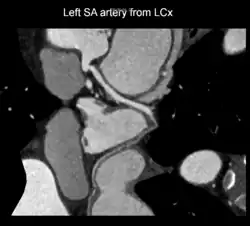

A left S-shaped sinoatrial artery, originating from the proximal left circumflex or LCx artery, has been described as a common variant in approximately 10% of human hearts.[5] This artery is larger than normal and supplies a good part of the left atrium, but also right-sided structures like part of the sinoatrial node and the atrioventricular nodal areas. In this variant, the artery courses in the sulcus between the left superior pulmonary vein and the left atrial appendage where it could be susceptible to injury during catheter or surgical ablation procedures on the left atrium, especially for atrial fibrillation ablation or open-heart cardiac surgery.